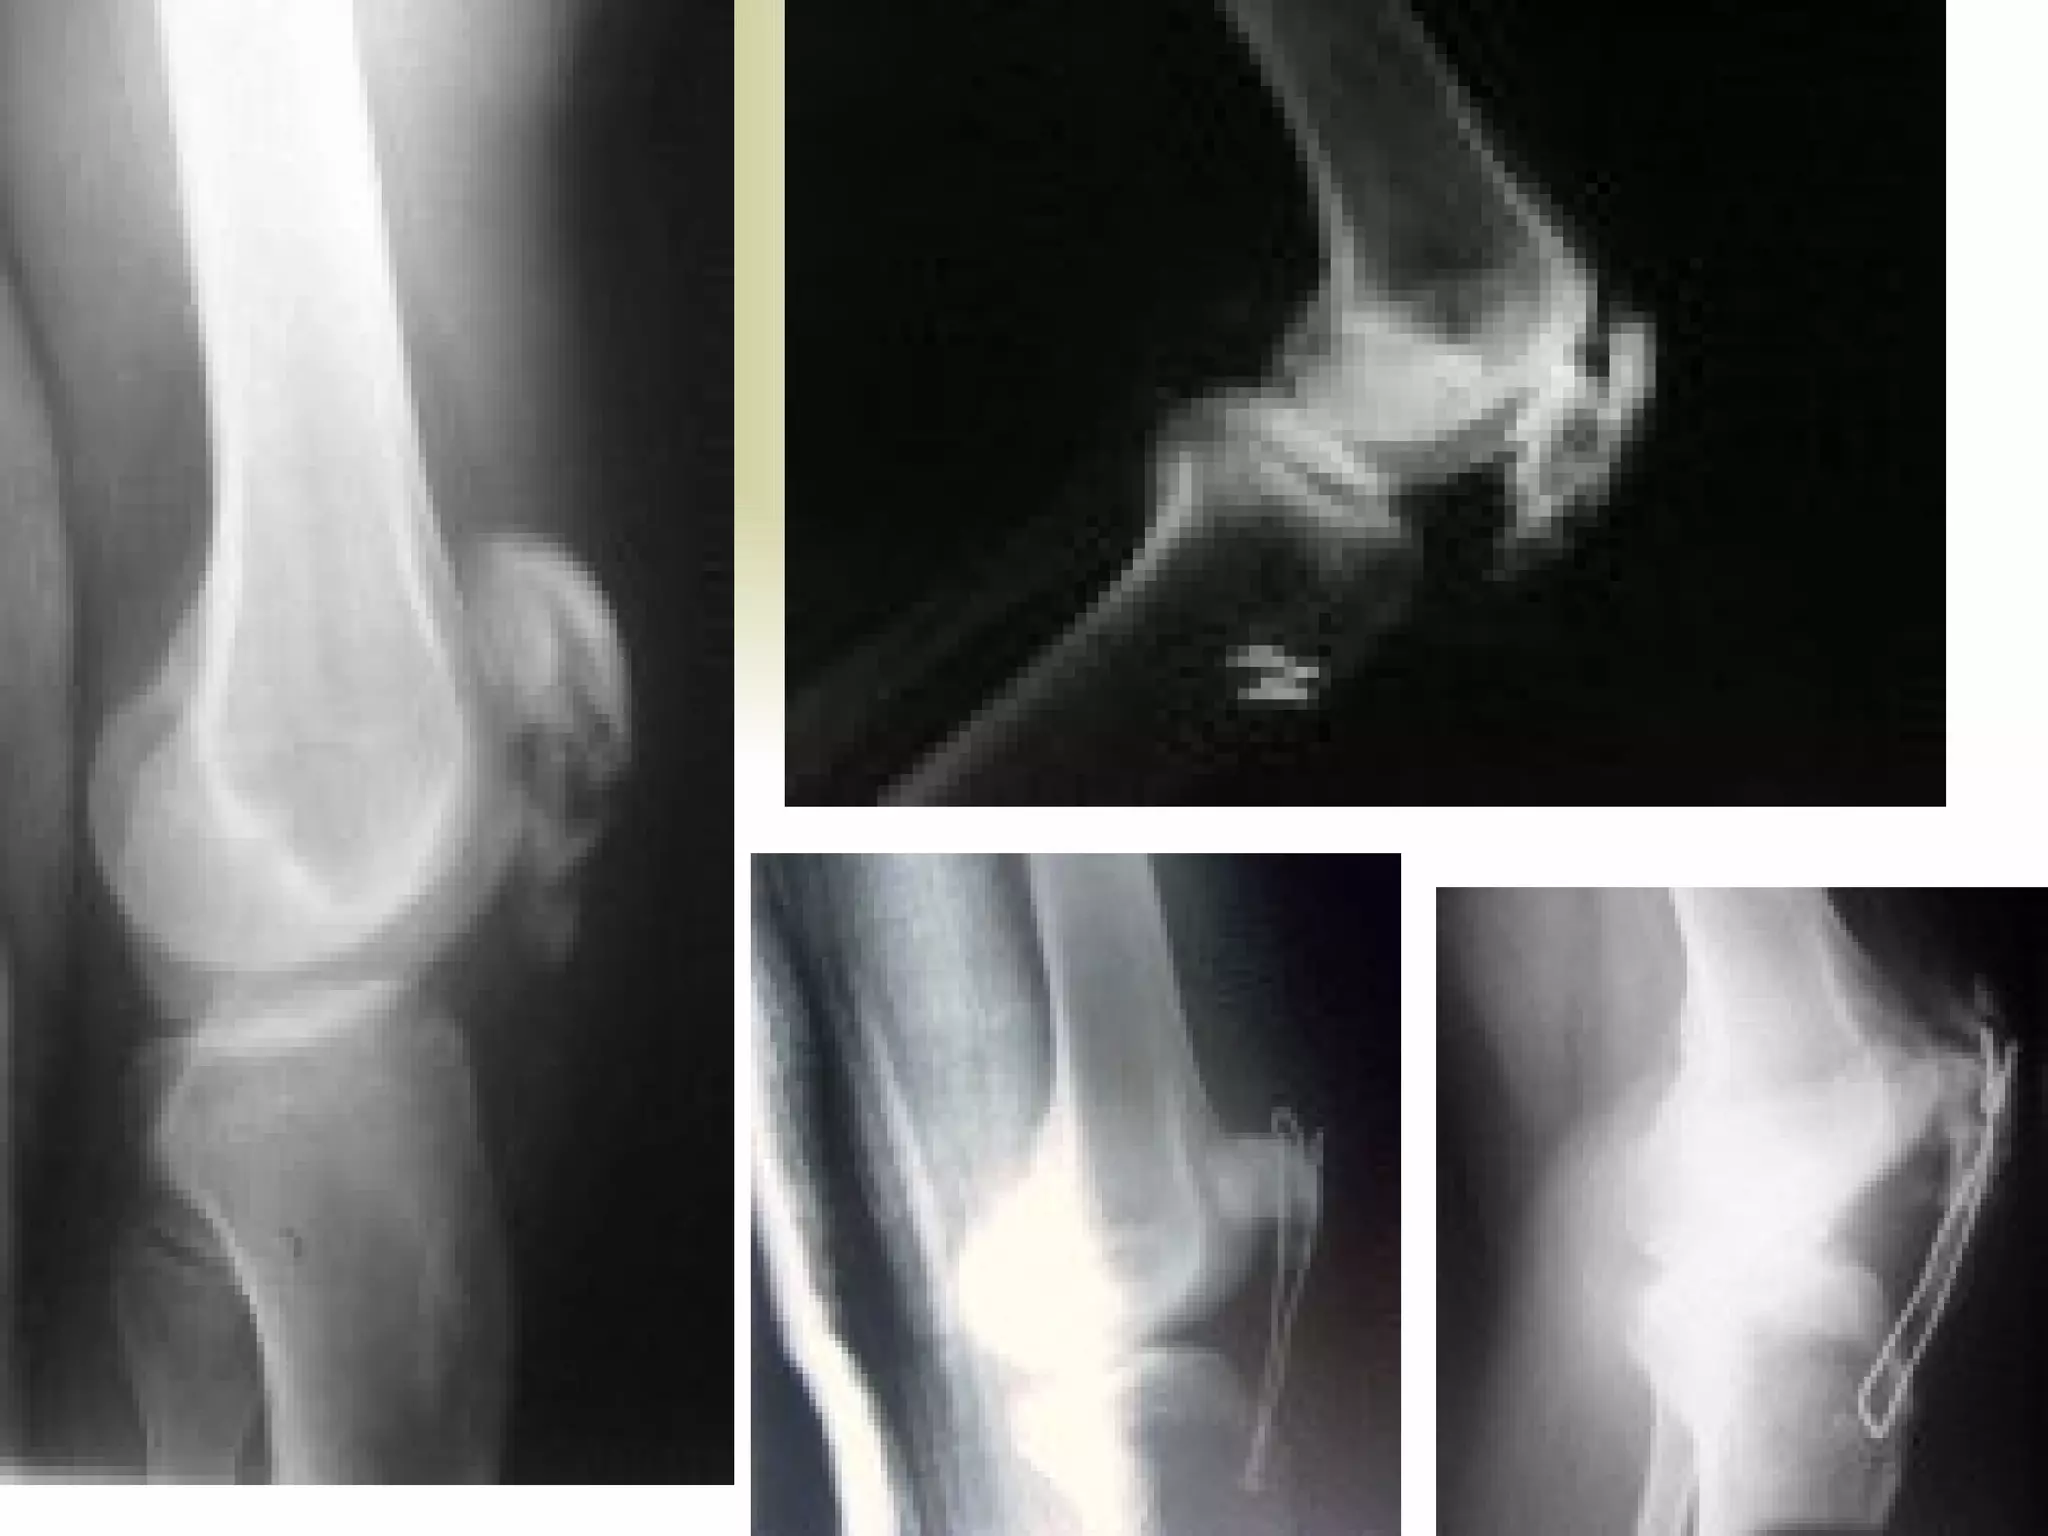

There are three types of patella dislocation: acute, recurrent, and habitual. Acute dislocation occurs suddenly due to quadriceps contraction with the knee flexed and results in the patella dislocating laterally, causing pain, swelling, and inability to straighten the knee. Recurrent dislocations are caused by ligament laxity or anatomical abnormalities and damage bones with repeated dislocations. Habitual dislocations occur every time the knee is flexed and present in early childhood.